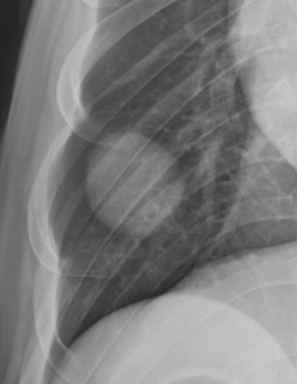

| Nodular pattern | 흰색 점이 생기면 |

결절

여러 개의 결정이 작았는데 점점 커짐 - >폐 종양성 전이